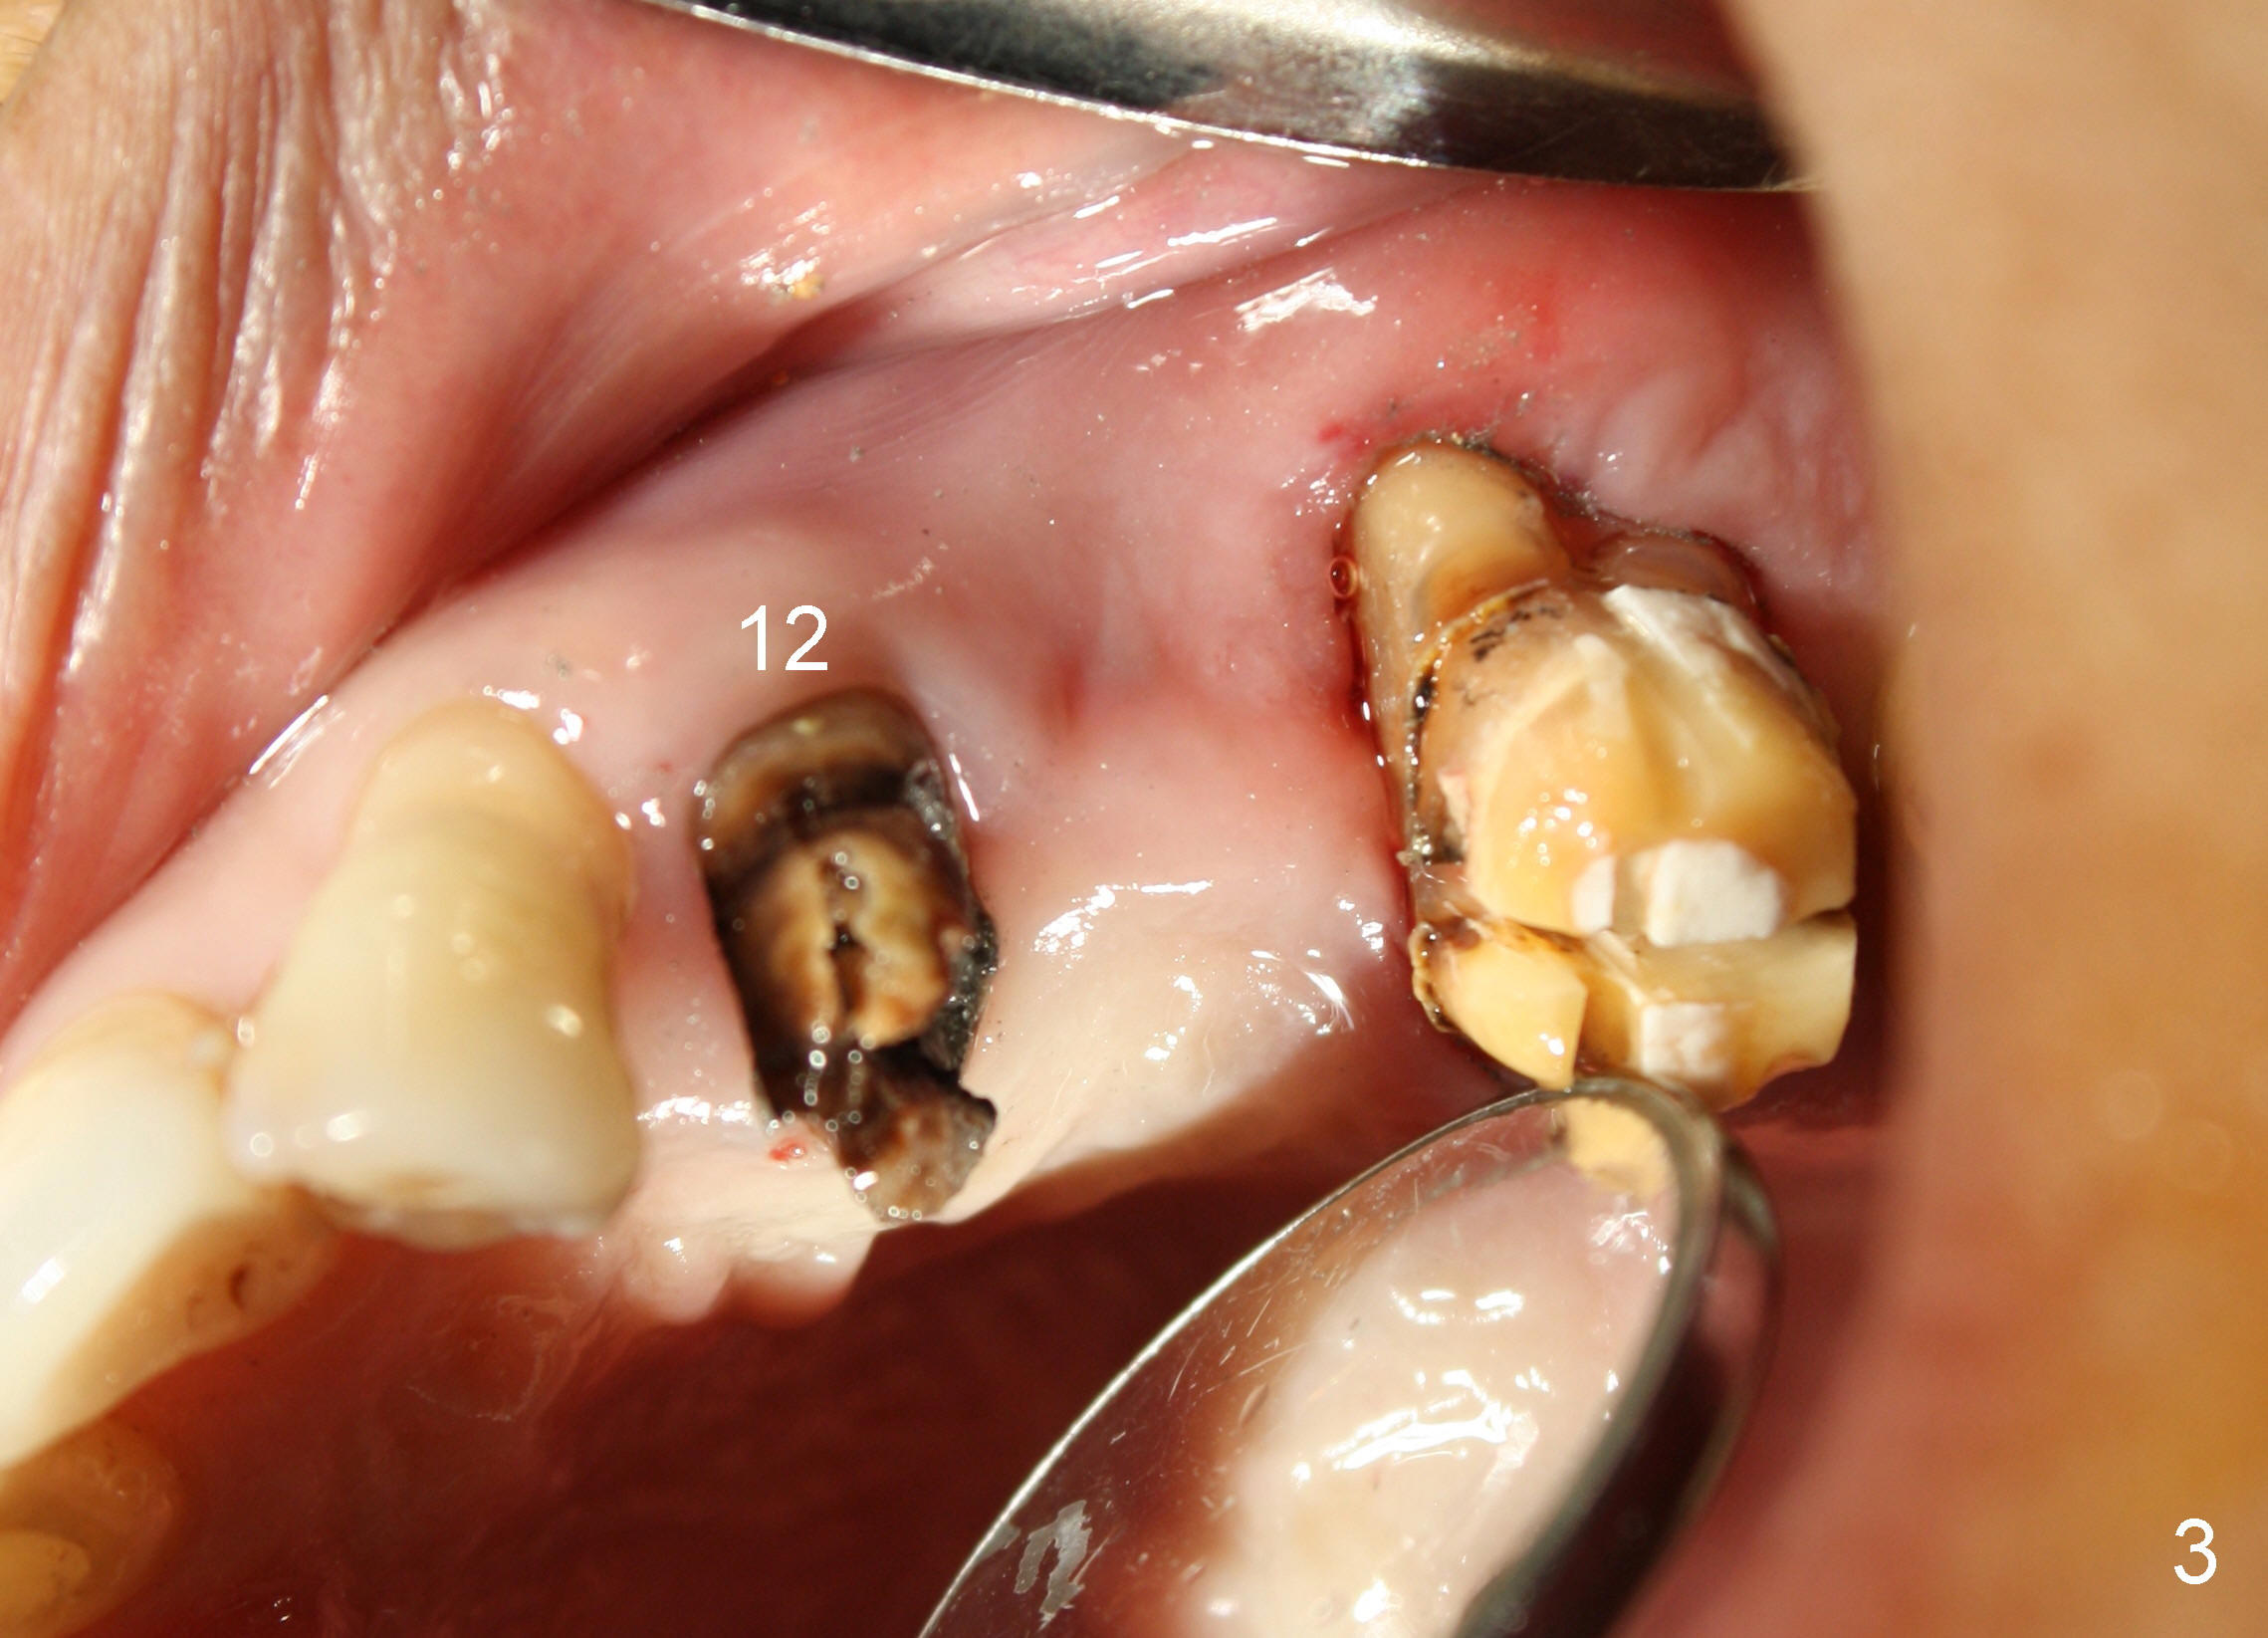

A 53-year-old lady has a failing bridge (Fig.1). There is severe bone loss around the buccal roots of #14 (*). Purulent discharge is from the gingival sulcus (Fig.2 <) with localized gingival erythema and edema (*). When the bridge is removed, the tooth #12 is found nonsalvageable (Fig.3,4). These two teeth are to be replaced by immediate implants (Fig.5). Although the sinus floor is low buccally (arrowheads), a 6x14 mm gingiva-level implant can be placed in the septum close to the palatal socket or in the palatal socket at the site of #14.